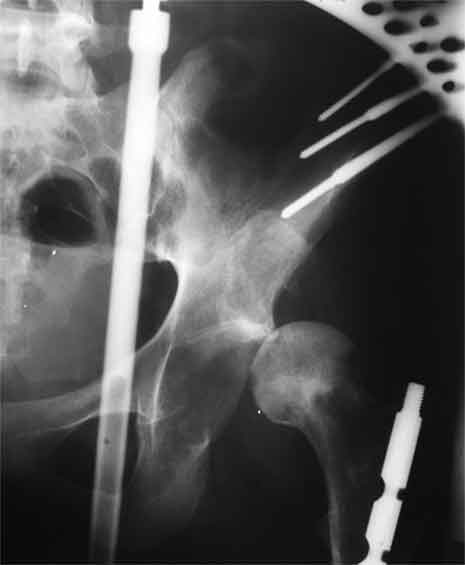

Насчет 8 см согласен с А.Н. Челноковым, это наверное ортопедическое за счет приводящей, сгибательной контрактуры и, возможно, колена. на ликвидацию укорочения у нас обычно уходит около 2-х нед. снимки в приложении, возможно не очень показательные, но других с ходу не нашел, завтра еще поищу.

Еще пара фото, ситуация несколько иная, задачи те же, открытое вправление застарелого вывиха в 2002, молодой возраст. Сейчас госпитализирована для эндопротезирования.